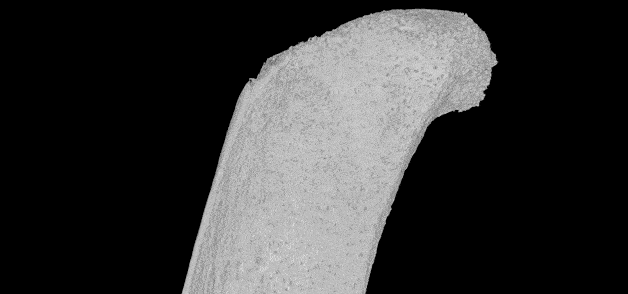

Схема строения транскортикального сосуда, проходящего через компактное вещество длинной кости. © Nature

Затем специалисты применили комбинацию нескольких методик, в том числе световой флуоресцентной микроскопии и рентгеновской микроскопии. Они заметили внутри костей, составляющих голень мыши, несколько сотен крошечных кровеносных сосудов, проходящих через твердый внешний слой.

Оказалось, что мышиная большеберцовая кость, которая по размерам меньше спички, может содержать более тысячи таких маленьких сосудов. Что удивительно, через их сеть проходит более 80 процентов артериальной крови и около 59 процентов венозной крови.

На следующем этапе команда решила проверить наличие подобных сосудов в костях человека. В результате оказалось, что кости людей также пронизаны сетью из сосудов нового типа, но более широкими по сравнению с мышиными.